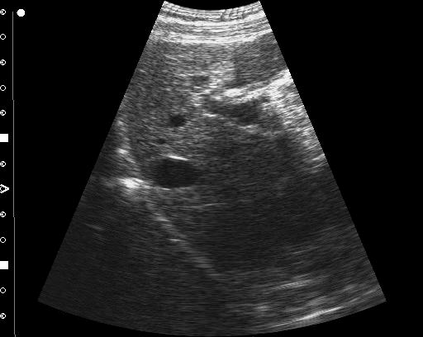

Most deep neural networks (DNNs) based ultrasound (US) medical image analysis models use pretrained backbones (e.g., ImageNet) for better model generalization. However, the domain gap between natural and medical images causes an inevitable performance bottleneck. To alleviate this problem, an US dataset named US-4 is constructed for direct pretraining on the same domain. It contains over 23,000 images from four US video sub-datasets. To learn robust features from US-4, we propose an US semi-supervised contrastive learning method, named USCL, for pretraining. In order to avoid high similarities between negative pairs as well as mine abundant visual features from limited US videos, USCL adopts a sample pair generation method to enrich the feature involved in a single step of contrastive optimization. Extensive experiments on several downstream tasks show the superiority of USCL pretraining against ImageNet pretraining and other state-of-the-art (SOTA) pretraining approaches. In particular, USCL pretrained backbone achieves fine-tuning accuracy of over 94% on POCUS dataset, which is 10% higher than 84% of the ImageNet pretrained model. The source codes of this work are available at https://github.com/983632847/USCL.